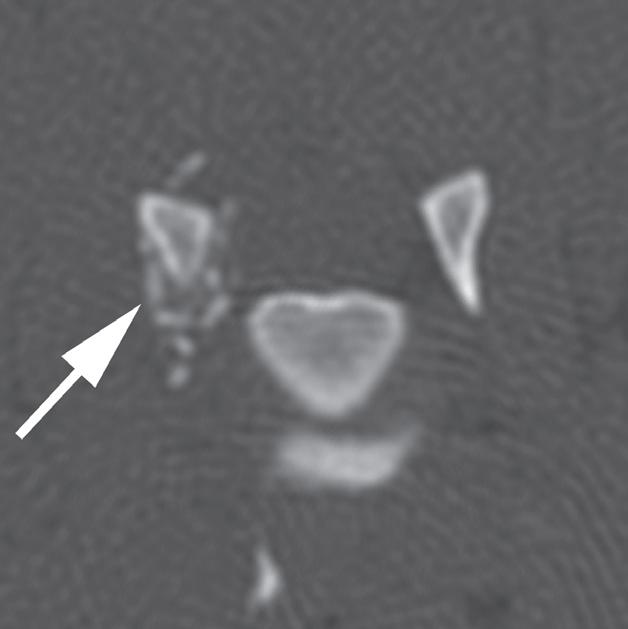

Rycina

3.2.8. Podwichnięcie kręgów szyjnych ze złamaniem wyrostka stawowego (pies) TK i MR

Badania wykonano u 5-letniej samicy mieszańca w typie teriera, która została pogryziona w okolicy szyjnej przez większego psa tego samego dnia, w którym wykonano badania. Podczas wizyty u psa zaobserwowano deficyty neurologiczne z neuroanatomiczną lokalizacją w obrębie C6–T2. Radiogramy przeglądowe ukazały grzbietowe podwichnięcie kręgu C7 względem C6 oraz zwężenie przestrzeni międzykręgowej C6–C7 (a – grot strzałki). Podobne zmiany uwidoczniono na obrazach TK w projekcji strzałkowej i 3D (b, f – grot strzałki). Dodatkowo stwierdzono wieloodłamowe złamanie z przemieszczeniem prawego doczaszkowego wyrostka stawowego kręgu C7 (c–e – strzałka). Dla porównania przedstawiono prawidłowy lewy wyrostek stawowy (f – strzałka). W badaniu MR przestrzeń międzykręgowa C6–C7 była zwężona i wykazywała obniżoną intensywność sygnału w obrazach T2-zależnych (i – strzałka), a przemieszczony materiał dyskowy znajdował się w prawej dobrzusznej części kanału kręgowego (g, h – grot strzałki). W obrazach występują cechy ucisku na rdzeń kręgowy (g–i) oraz zwiększona intensywność sygnału w sekwencji T2-zależnej w obrębie rdzenia na poziomie C6–C7 (h, i), co wskazuje na jego uszkodzenie wewnętrzne. Materiał dyskowy został chirurgicznie usunięty z kanału kręgowego, a podwichnięcie zredukowano i ustabilizowano operacyjnie